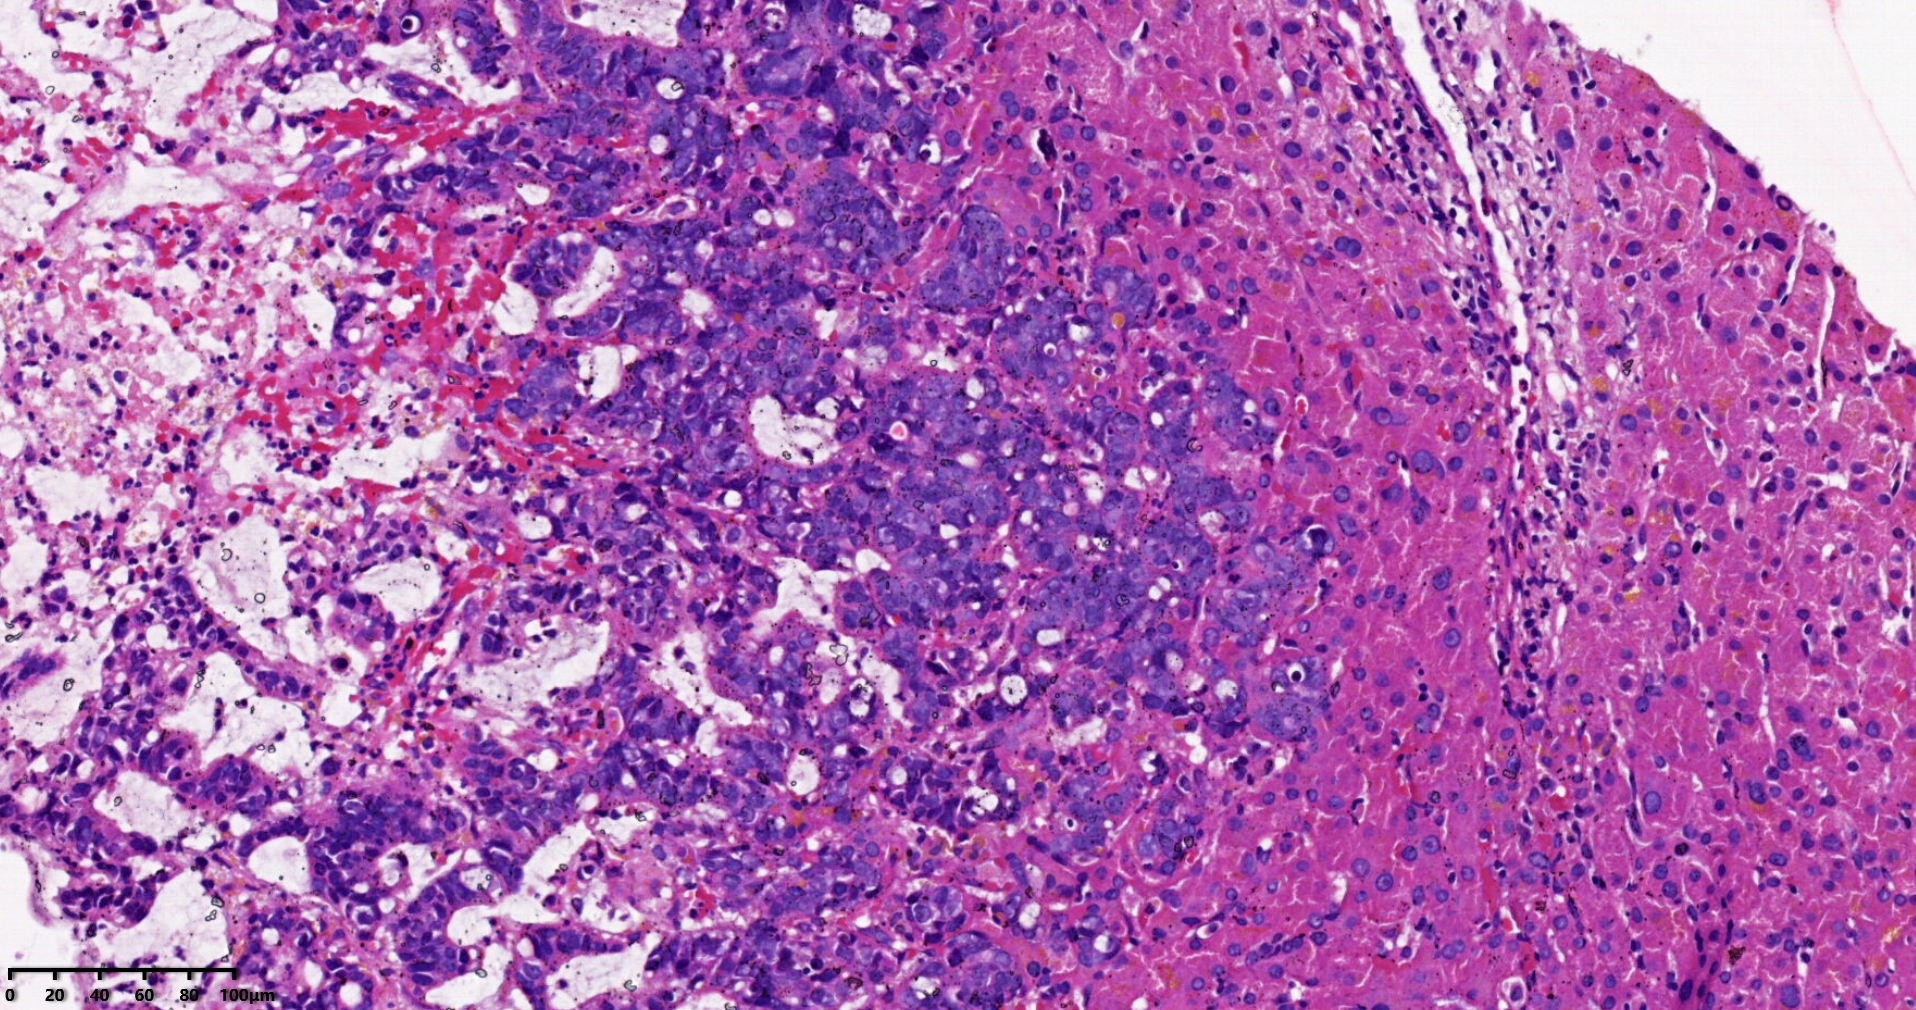

考虑符合:肝内胆管癌

• rys114:  老师,免疫组化ck7-,ck20+,支持诊断吗?

• whyang315:  当然!

考虑转移性黏液腺癌,消化道来源可能,建议做免疫组化,排除胆管源性。